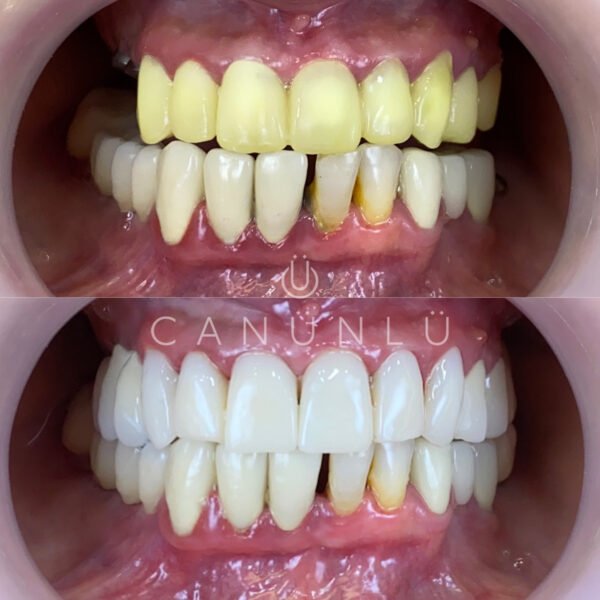

İmplant nedir?

Diş İmplantları, eksik olan dişlerin yerine, çene kemiğine yerleştirilen titanyumdan yapılmış vidalardır. İmplantlar, küçük bir cerrahi işlemle çene kemiğine yerleştirilir. Bu işlemden sonra üç ay gibi kısa bir sürede tamamen çene kemiğine tutunur. Bu tutunma sonrası implant gerçek bir diş kökünün yerini alarak üzerine yapılacak protezi taşımaya hazır hale gelir.